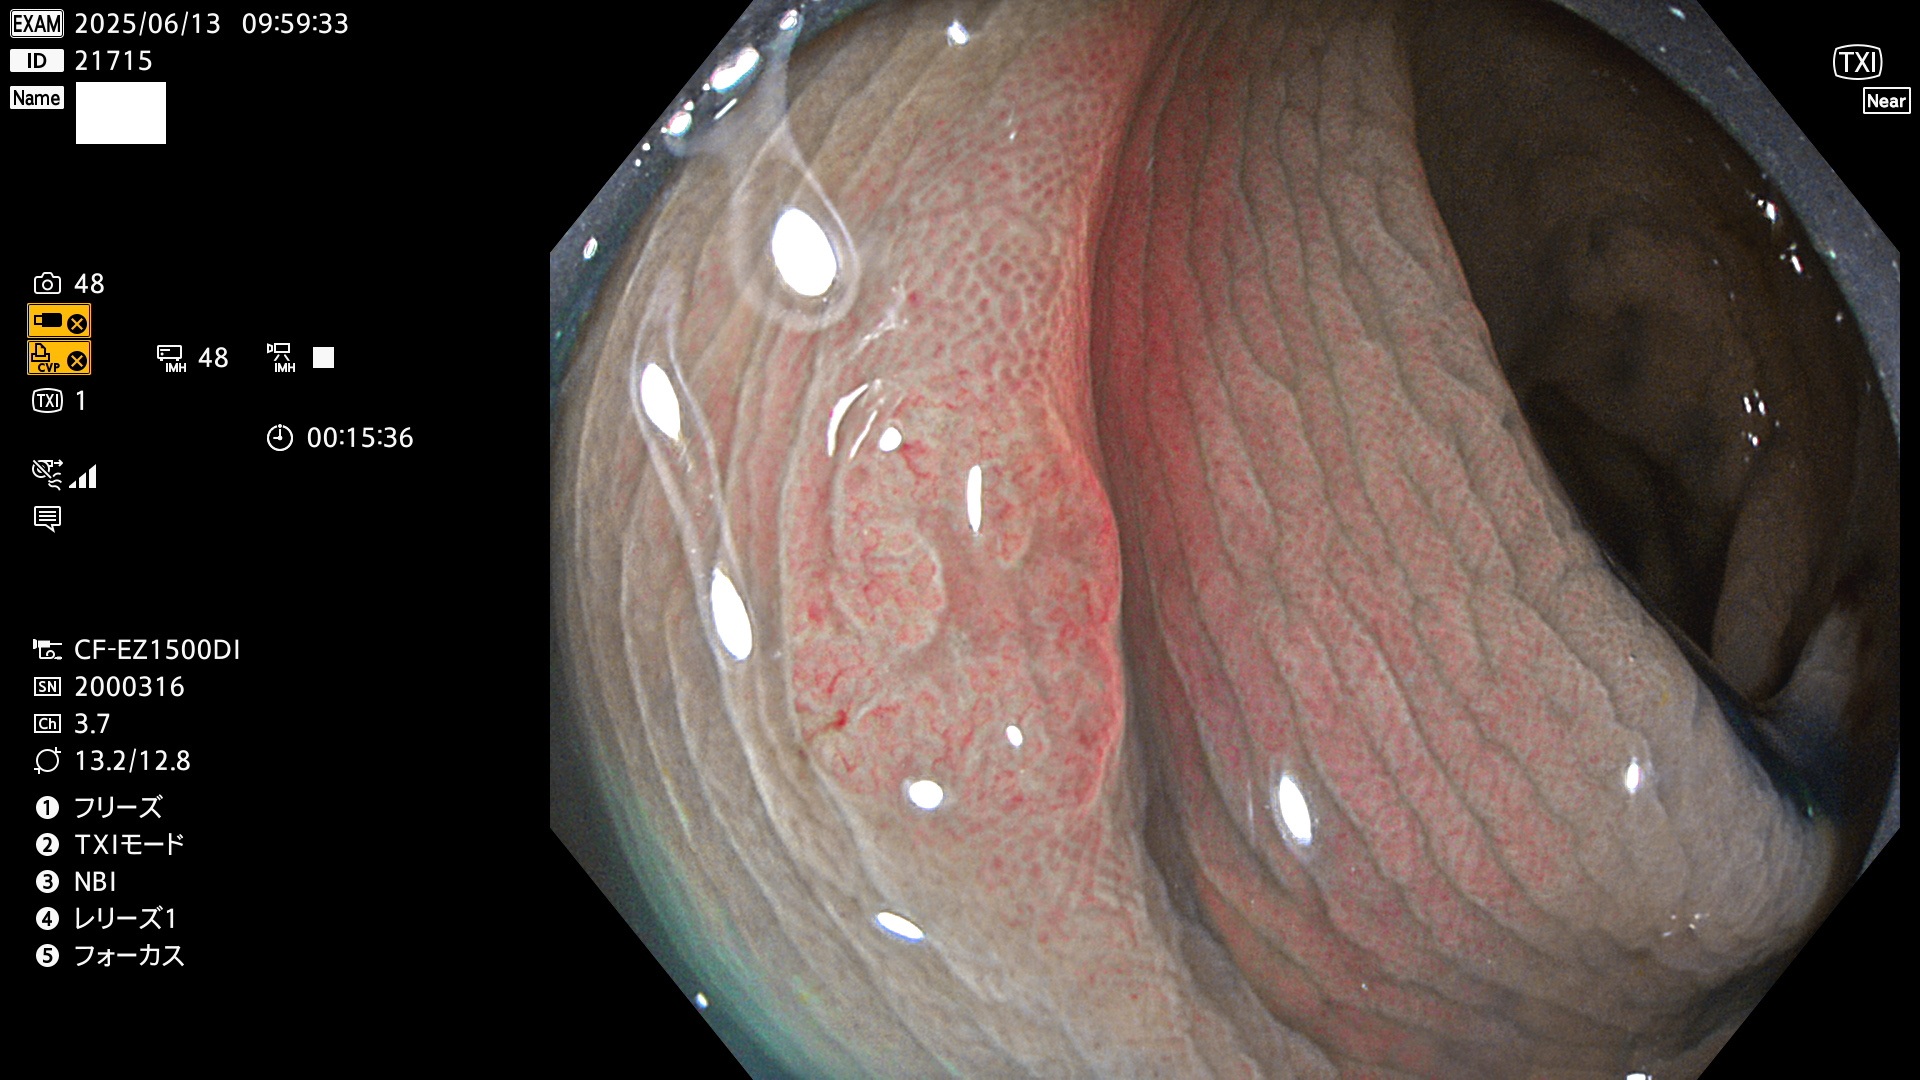

完全に平坦な物をUb、陥凹している物をUcと呼びます。Ubは認識が困難で、Ucはびらん(炎症)と紛らわしいために見落とされやすく、「内視鏡後・大腸癌」の原因になります。

抽出の対象期間 2025年6月12日〜6月15日の4日間(48件の検査)14個 (14/48=29%)